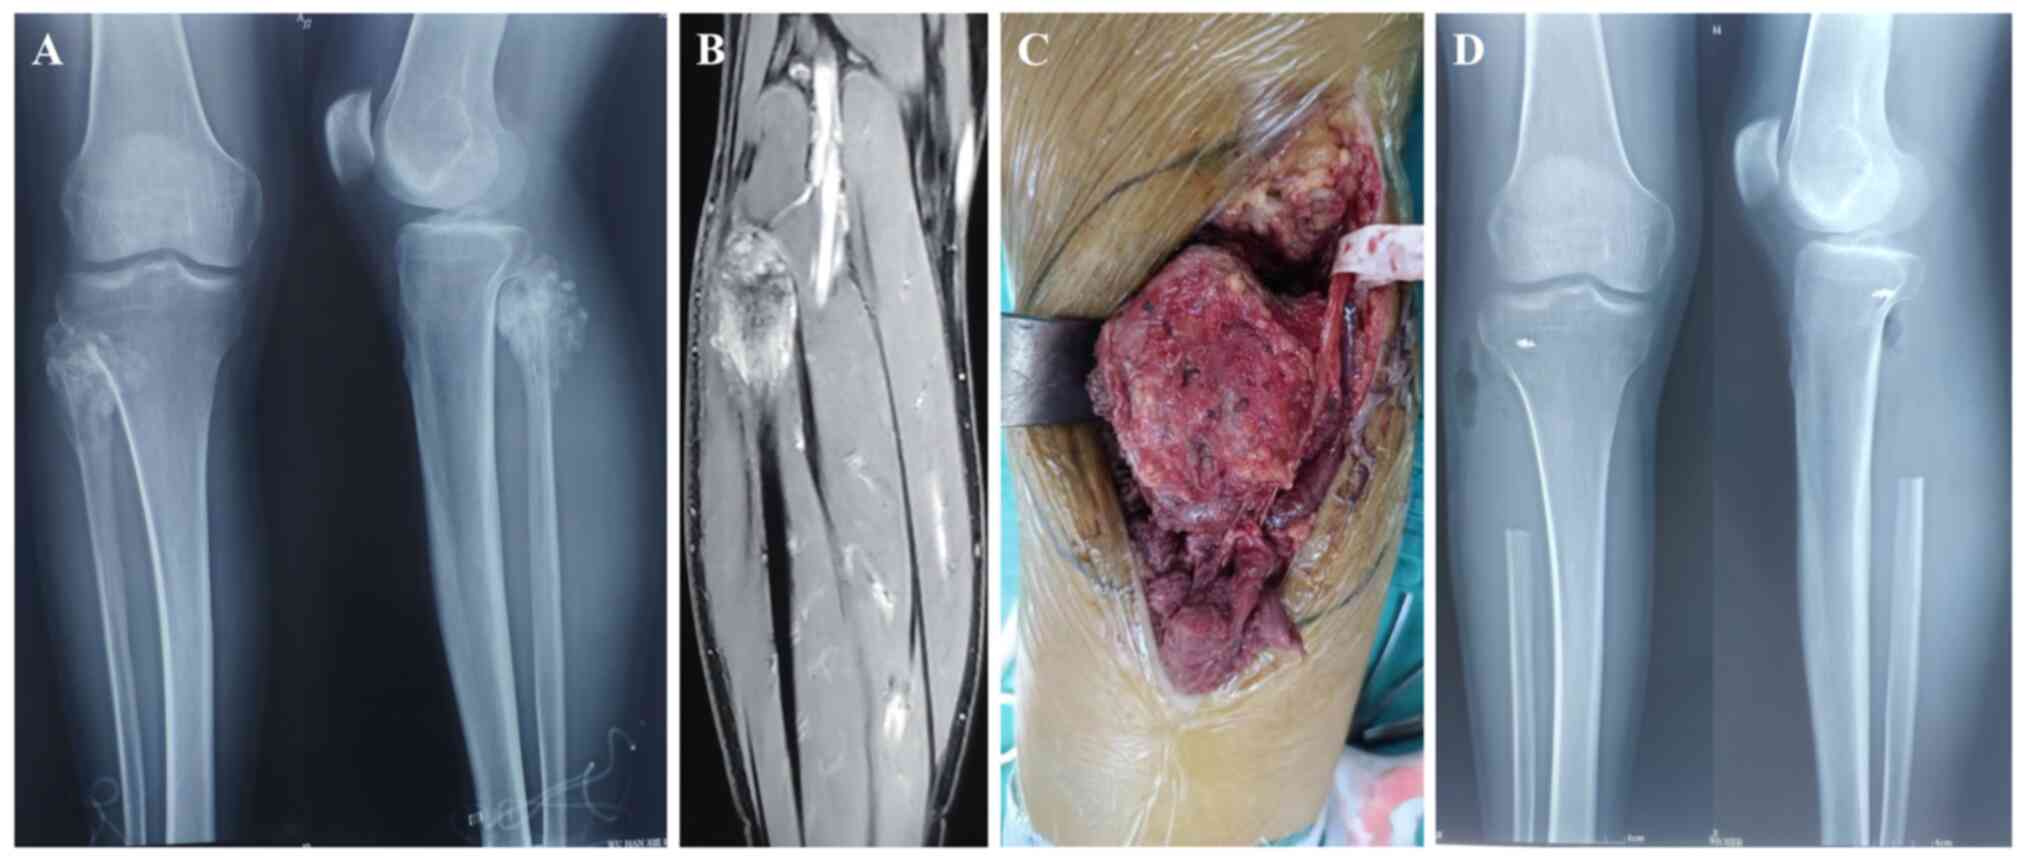

The basic information of the patients is listed in Table I; according to pathological classification, there were 10 osteosarcoma cases, 3 chondrosarcoma cases, 2 invasive giant cell osteosarcoma tumour cases, 1 epithelioid sarcoma case, 1 leiomyosarcoma case, 1 fibrosarcoma case and 1 lymphoma case. According to the Enneking classification, IB stage was found in 2 cases, IIA in 2 cases and IIB in 15 cases. The indicators of treatment modalities and prognostic follow-up are listed in Table II; a total of 3 patients underwent Malawer I resection, and 16 patients underwent Malawer II resection. The follow-up time was 11-174 months, with an average of 76.58 months. None of the patients had incision infection or skin necrosis; however, there were two patients with common peroneal nerve injury. Local recurrence occurred in three patients (two with osteosarcoma and one with leiomyosarcoma); all three patients underwent Malawer I resection. In addition, one patient underwent amputation, one patient underwent extensive resection and one patient underwent local radiotherapy. Seven patients developed pulmonary metastasis, of which four of these patients succumbed. After the resection of proximal fibula primary and invasive tumours, the biceps femoris tendon and lateral collateral ligament insertion point was reconstructed. After the reconstruction of the biceps femoris tendon and lateral collateral ligament, knee joint function was stable in all but one patient who reported self-perceived instability of the knee joint. The MSTS score at the last postoperative follow-up was 23-29 points, with an average of 27.26 points (90.87%; postoperative MSTS score divided by total MSTS score). The LKS was 65-84 points, with an average of 83 points. Most patients experienced pain relief and their daily life was not affected. Patients with permanent common peroneal nerve palsy needed to wear braces to walk after surgery. Two typical cases are presented in the figures, including an invasive giant cell tumour of the proximal right fibula treated with Malawer I resection (Fig. 1), and a chondrosarcoma of the proximal left fibula treated with Malawer Ⅱ resection (Fig. 2).

A chondrosarcoma of the proximal left fibula treated with Malawer Ⅱ resection. (A) Pre-operative X-ray imaging showing the irregular bone destruction with calcification of proximal fibula. (B) MRI showing inhomogeneous high signals in intramedullary lesions and soft tissue masses. (C) The tumour invaded the common peroneal nerve. (D) Postoperative X-ray examination showing good stability of the knee joint.